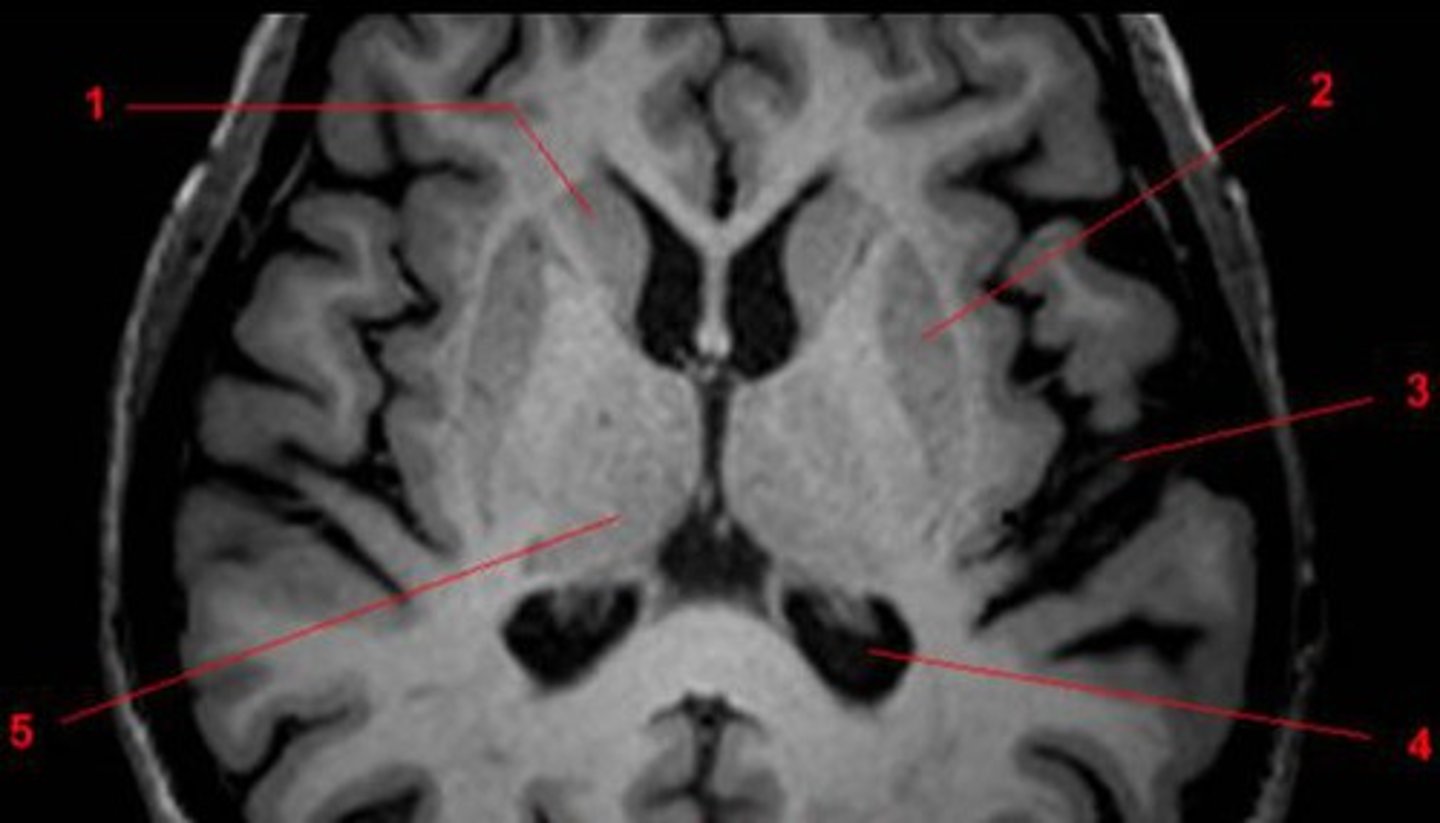

Horizontal or Axial View